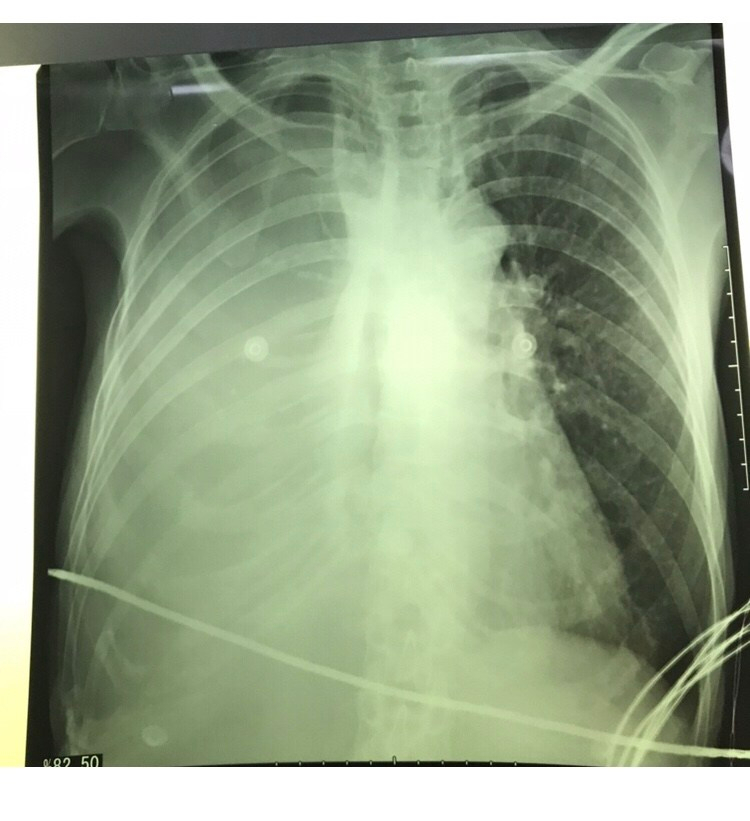

RX de torax no leito: opacidade difusa em hemitorax direito, área cardíaca normal

US à beira leito: lextenso derrame pleural à direita com presença de grumos